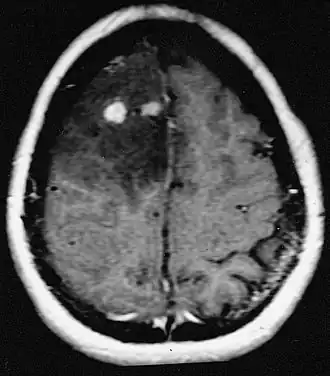

![]() Resonancia magnética de astrocitoma fibrilar difuso con diferentes grados de diferenciación. | ||

Los astrocitomas difusos son tumores cerebrales de lento crecimiento, los más frecuentes entre los gliomas de bajo grado. Afectan principalmente a niños y adultos jóvenes, de 20 a 40 años. Son clasificados como tumores de grado II por la OMS.[1][2] Histológicamente se han descrito 3 subtipos: astrocitoma fibrilar, protoplásmico y gemistocítico.[3]

Para realizar el diagnóstico el médico puede realizar un examen neurológico o utilizar pruebas de EEG que ayudan a revelar el tamaño, localización y velocidad de desarrollo del tumor. Las tomografías computarizadas y resonancias magnéticas del cerebro pueden mostrar la presencia de una masa difusa que no se ilumina cuando se administra un medio de contraste. En algunos casos, es posible que se requiera una biopsia para confirmar la naturaleza del tumor.[5]